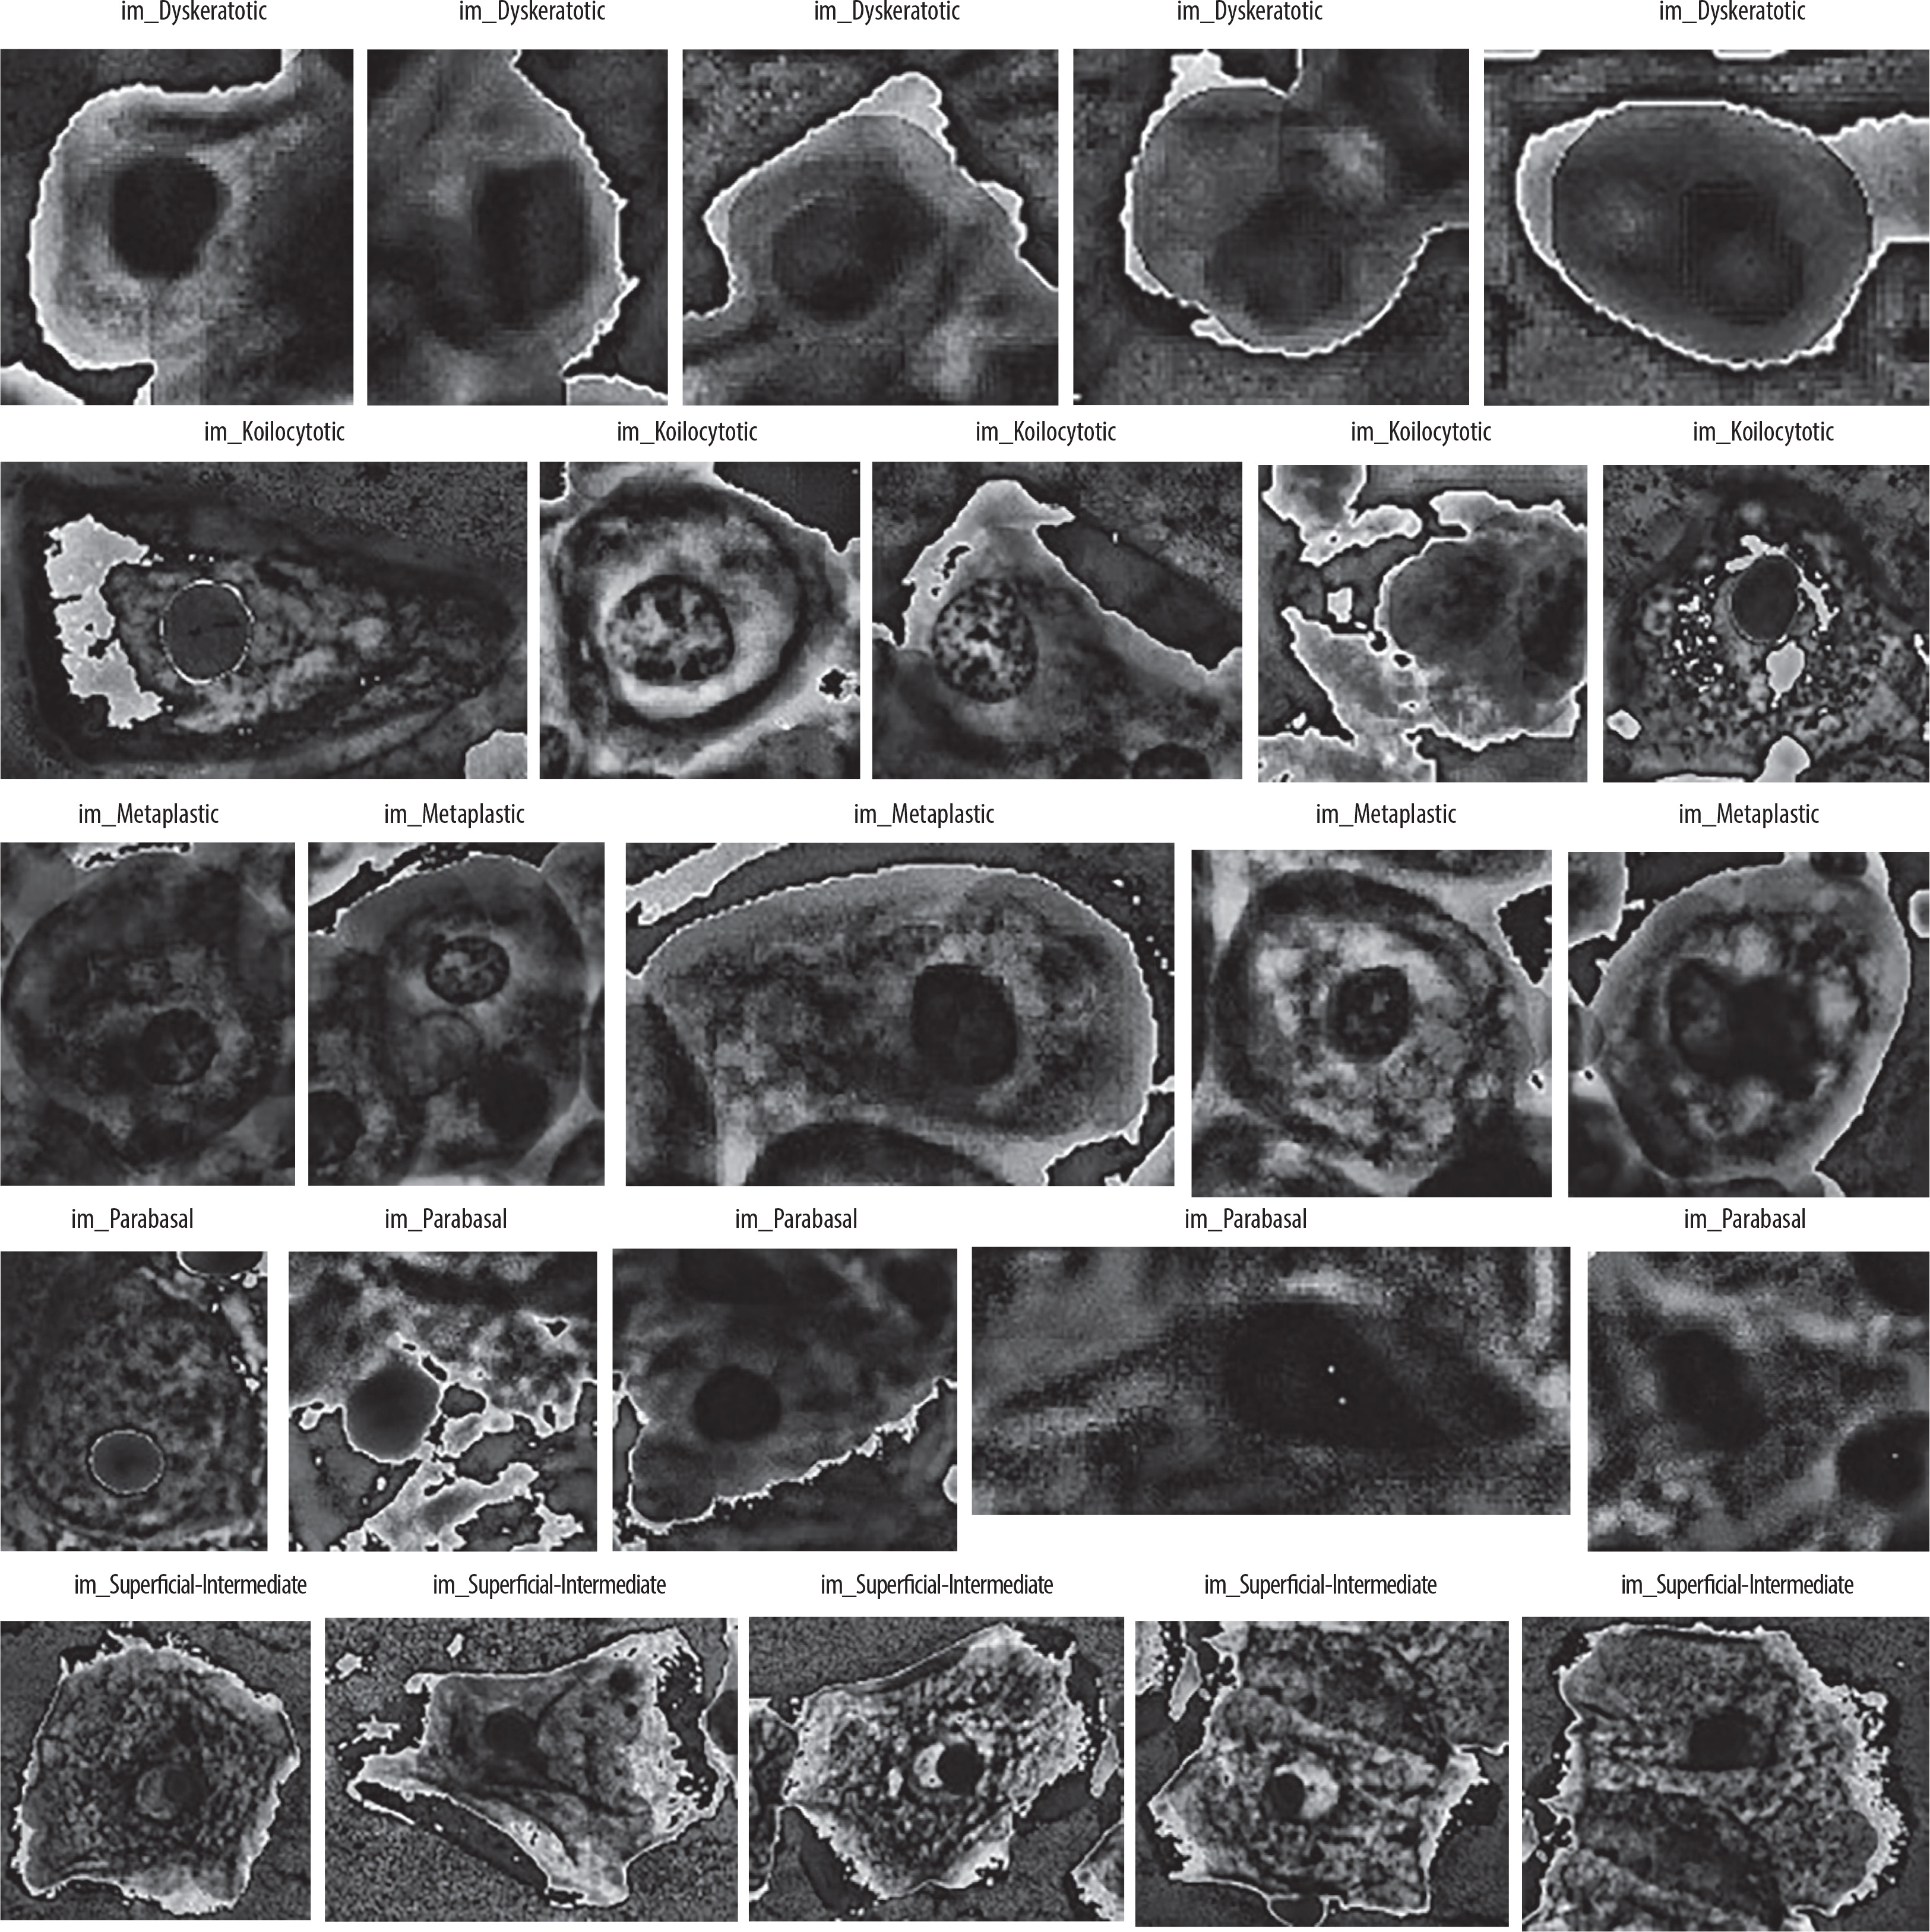

SIPaKMeD is an open-source dataset, which was used in the study. This dataset contains a total of 4049 single-cell images, which were manually retrieved from 966 cell cluster images of Pap-smear slides. Microscopic images of cells are captured with the help of a CCD camera and an optical microscope. Normal cells, abnormal cells, and benign cells fall into 5 categories: dyskeratotic, metaplastic, parabasal, koilocytotic, and superficial-intermediate (Figure 1).

A dyskeratotic cell is a squamous cell that has undergone premature abnormal keratinisation within an individual cell or in clusters. Despite being orangeophilic, their cytoplasm is brilliant.

Koilocytic cells have vesicular nuclei similar to those of koilocytic cells. In many cases, cells with several nuclei are likely to be binucleated or multinucleated. The second category, koilocytotic cells, is mainly found in mature squamous cells, both superficial and intermediate. They appear mostly cyanophilic, very lightly stained, and characterized by a large perinuclear cavity.

Metaplastic cells are either small or large parabasal-type cells characterised by distinct cellular boundaries, sometimes exhibiting eccentric nuclei and occasionally possessing a substantial intracellular vacuole. The central staining is often light brown and contrasts with the marginal staining. The subsequent group, parabasal-cells, comprises immature squamous cells and represents the smallest type of epithelial cells seen in a standard vaginal smear. The cytoplasm is often cyanophilic and typically features a prominent vesicular nucleus.

Parabasal cells have morphological similarities to metaplastic cells, making differentiation between the 2 challenging.

The last group comprises the majority of cells obtained in a Pap test. They often present as flattened structures with round, oval, or polygonal cytoplasm, generally eosinophilic or cyanophilic. Their nucleus is centrally placed and pycnotic. Their cytoplasm is large and polygonal with well-defined boundaries, and the nuclear borders are immediately identifiable.